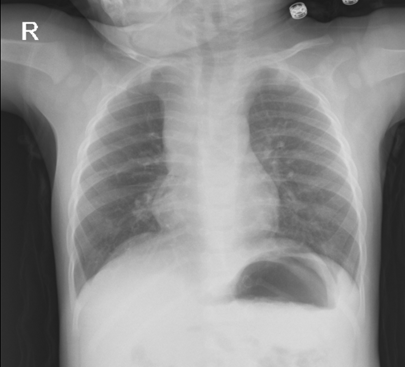

An 11-month-old boy applied to the Pediatric Emergency Service due to sudden respiratory distress. The patient's anamnesis was taken, and it was learned that he started to cough after eating cucumber. He had no respiratory complaints or other health problems in the last month. In the respiratory examination of the patient, rhoncus was heard in the bilateral lungs, other system examinations were normal. Chest radiography was not evaluated in favor of FBA in the first evaluation (Figure 1). Pneumonia was considered in the differential diagnosis because of bilateral infiltration on chest radiography and bilateral rhoncus on examination. The COVID-19 PCR test was negative. The patient was given inhaled salbutamol treatment, and respiratory distress did not regress after salbutamol treatment. When the chest radiography of the patient was examined in more detail, an area compatible with air trapping was observed in the right upper lobe (Figure 1). Bronchoscopy was performed on the patient, and a piece of cucumber with a size of 1X0.5 cm was removed (Figure 2). The patient whose complaints regressed after bronchoscopy was discharged with full recovery.

Figure 1 Chest X-ray of the case.

Diagnosis requires a good history, physical examination, radiological examination and bronchoscopy. Although there is generally a history of aspiration, classical findings suggesting foreign body aspiration accompanied by a sudden onset of cough, wheezing and decreased respiratory sounds have been reported in only 40-57% of the cases. Patients may be completely asymptomatic, and may present with different degrees of respiratory distress, atelectasis, chronic cough and recurrent pneumonia, or even death within minutes. Complaints begin within seconds and sometimes minutes after aspiration. After a while, these complaints may regress completely, which leads to a late diagnosis.11-15 When our case came with sudden respiratory distress, it was learned that it happened after eating cucumber as a result of the story. FBA was suspected, as she had bilateral rhonchi in her respiratory examination. In our case, there was no clear FBA finding on chest radiography.

The first diagnostic method used in cases with suspected foreign body is chest radiography and chest radiography is reported as normal in 10-40% of cases. For radiopaque bodies, chest radiography is very important in the diagnosis, while radiolucent bodies are seen as segmental or lobar collapse, increased localized aeration, atelectasis, infiltration and bronchiectasis.8 In our case, first FBA finding was not considered on chest radiography, detailed examination was considered to be compatible with air trapping in the right upper lobe. Although it is inexpensive and easily accessible, chest radiography should not be considered reliable in the diagnosis of foreign body aspiration. In our case, chest radiography findings alone were not sufficient for diagnosis.